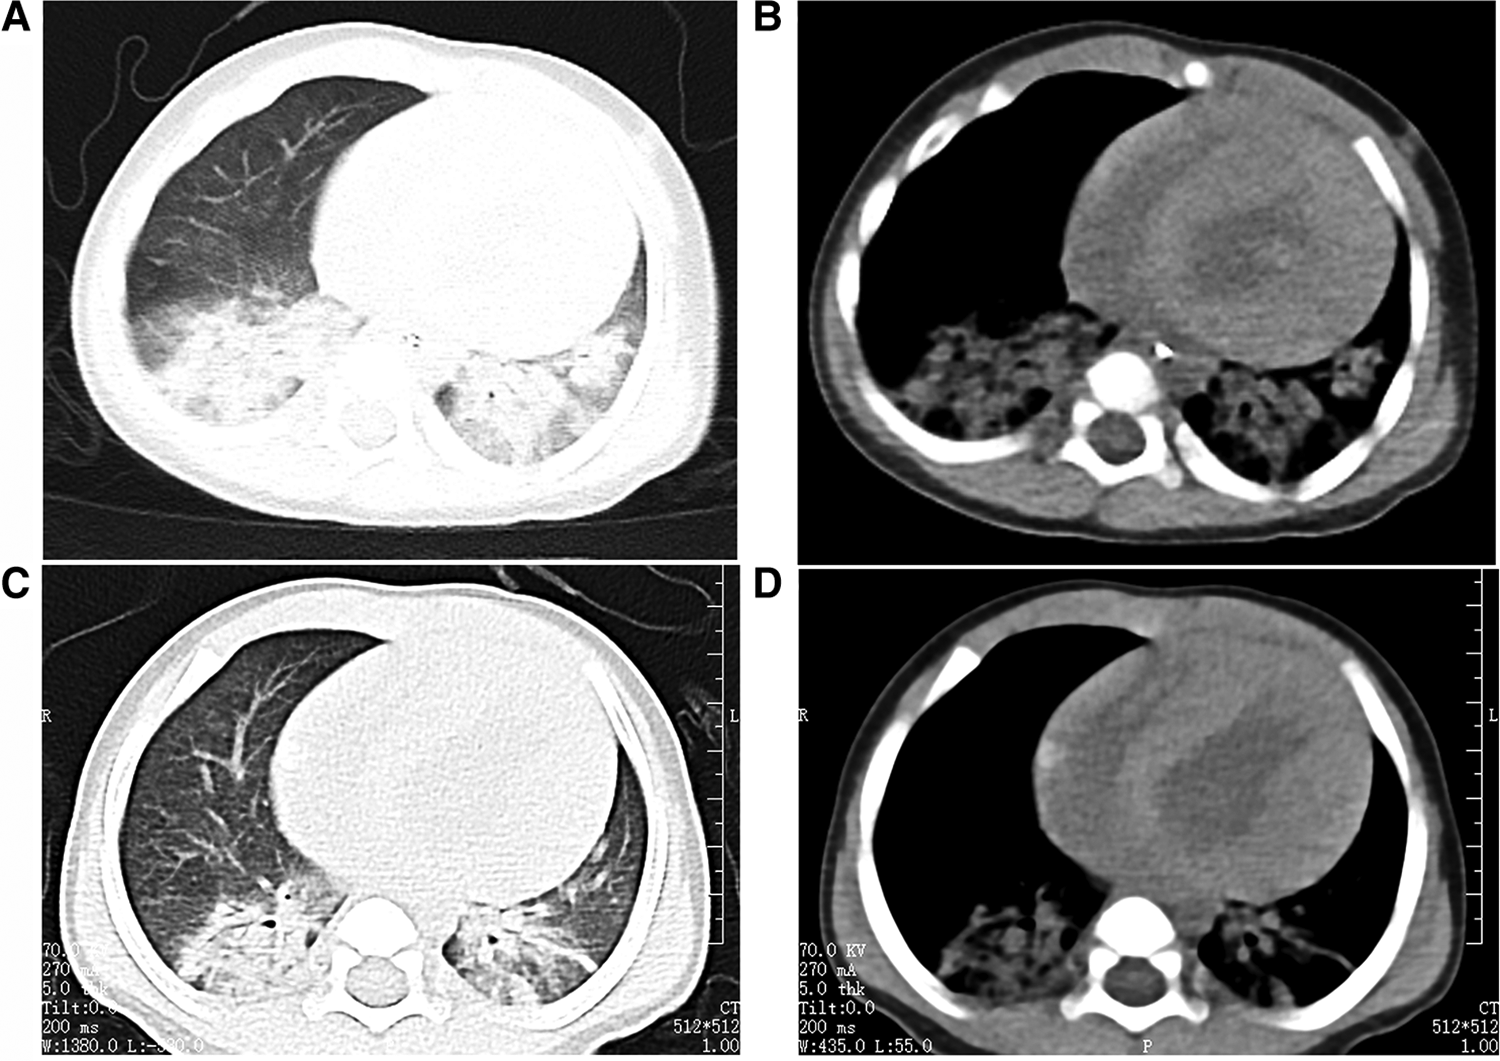

The cardiac echocardiography (Figures 1A–C) showed diffuse thickening of the left ventricular wall, with the anterior wall approximately 9.5 mm thick, the interventricular septum around 8 mm, the lateral wall about 9 mm, and the inferoposterior wall approximately 9 mm. The thickened myocardial wall had increased echogenicity and stiffness, with generally reduced movement amplitude. The endocardium of the left ventricle was thickened, up to about 5 mm. The ejection fraction (EF) was 62%, and the shortening fraction of the left ventricular short axis (FS) was 31%. Color Doppler Flow Imaging (CDFI) showed no shunt at the ventricular level. A small left-to-right shunt was observed at the middle of the interatrial septum (foramen ovale), approximately 2 mm wide. A small amount of regurgitation was noted at the mitral valve, and a trace regurgitation signal was seen at the tricuspid valve with a regurgitation speed of 1.8 m/s, estimating pulmonary artery pressure at 18 mmHg (right atrial pressure assumed to be 5 mmHg). The abdominal ultrasound showed hepatomegaly and edematous gallbladder walls. The chest CT scan revealed normal translucency in both lungs with disordered patterns, patchy areas of increased density, localized consolidation with visible air bronchograms, normal hilar shadows, and clear airways. The cardiac silhouette was enlarged, with thickening of the left ventricular myocardial wall (Figure 2A). The electrocardiogram showed sinus tachycardia, enlargement of the left atrium and left ventricle, accompanied by ST-T changes (Figure 3).

Figure 2

The child's chest CT scans indicated bilateral pneumonia. (A and B: before treatment, C and D: after treatment), with a significantly enlarged cardiac silhouette. After one week of treatment, the pulmonary imaging showed improvement, but there was no noticeable change in the size of the cardiac silhouette.

After one week of regular anti-infection treatment, liver protection, and heart function improvement, the infant's body temperature normalized, and a recheck showed a significant decrease in N-terminal pro-brain natriuretic peptide (1,730.94 pg/ml). CT scans indicated reduced lung inflammation (Figure 2B). However, a follow-up cardiac echocardiography (Figures 1D–F) still indicated symmetric hypertrophic cardiomyopathy (non-obstructive type) with thickening of the left ventricular endocardium, and decreased left ventricular systolic and diastolic function (EF 48%, FS 22%). The liver size had not noticeably reduced, and there was no improvement in the liver function tests (alanine aminotransferase and aspartate aminotransferase) compared to admission. Serum creatine kinase levels were 476 U/L, which was inconsistent with clinical expectations. This lack of noticeable improvement in the echocardiographic images underscores the severity and progression of the disease, despite the treatment efforts.